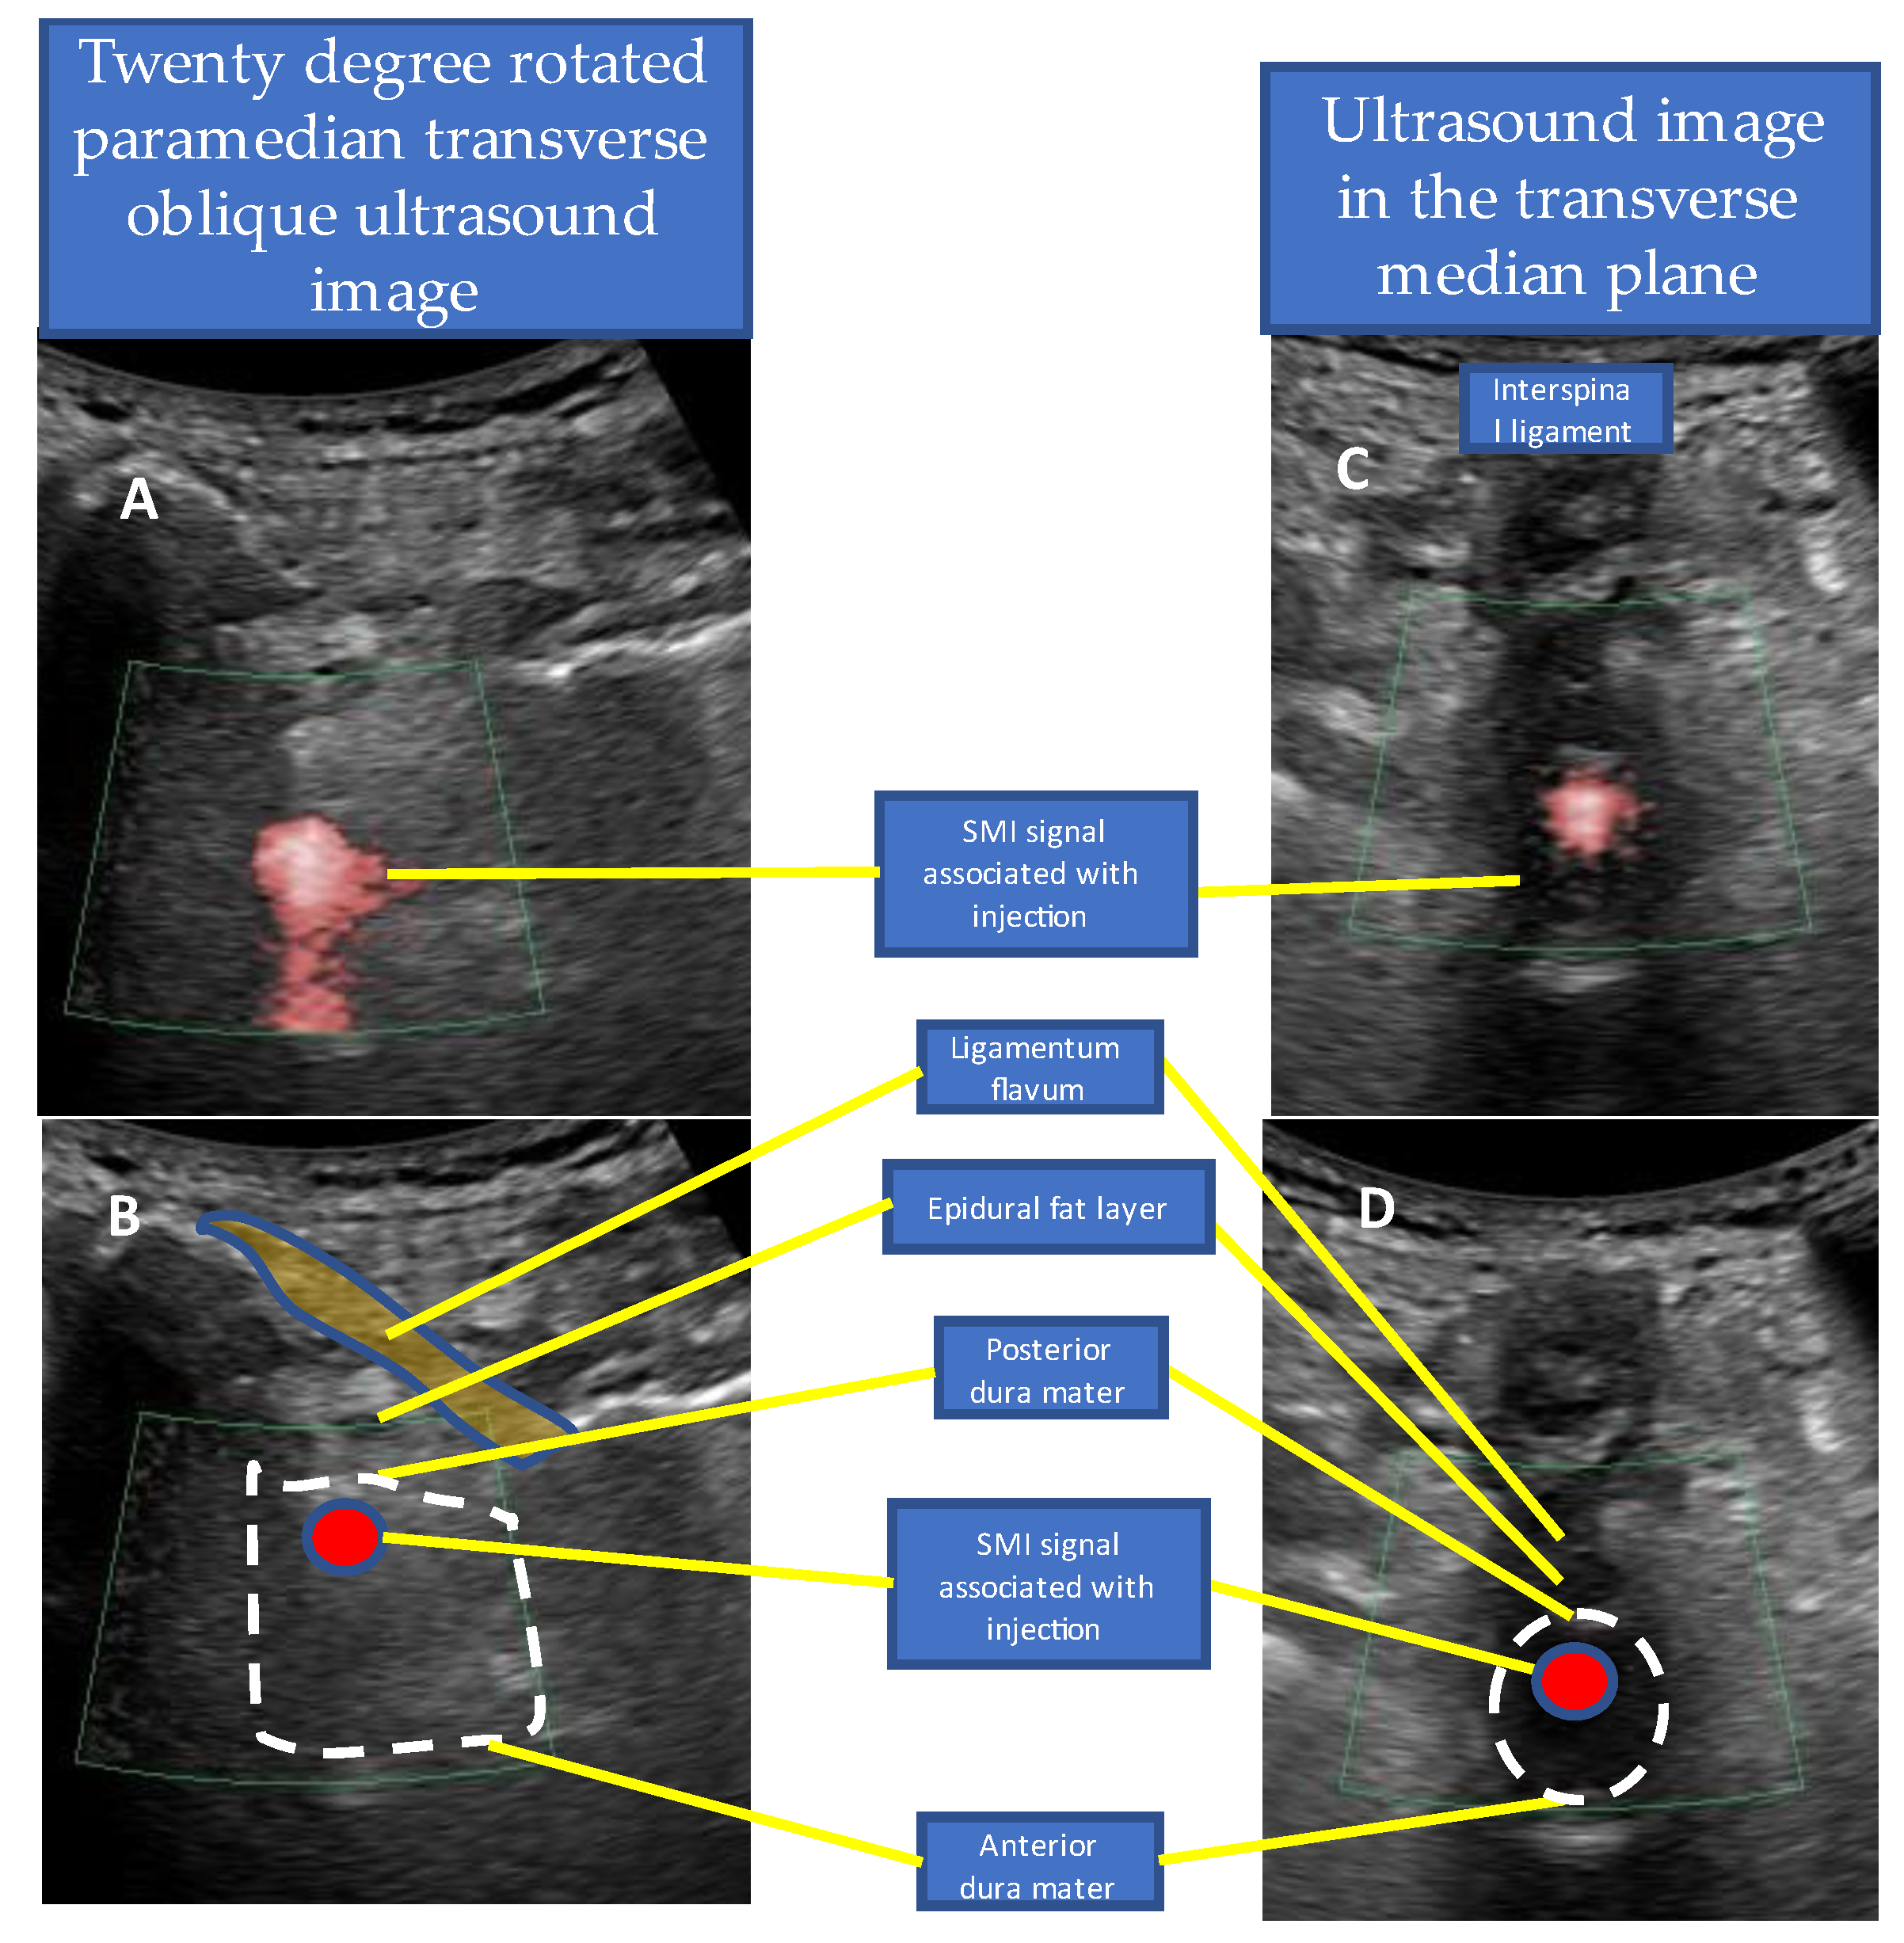

- Accurate needle tip guidance into the ligamentum flavum behind the epidural fat layer;

- Palpation of resistance by finger sense during ligamentum flavum insertion while confirming with sonography;

- Confirmation of the position of the needle tip in the ligamentum flavum;

- Tracing the spread of the drug in the epidural space using SMI during the injection.